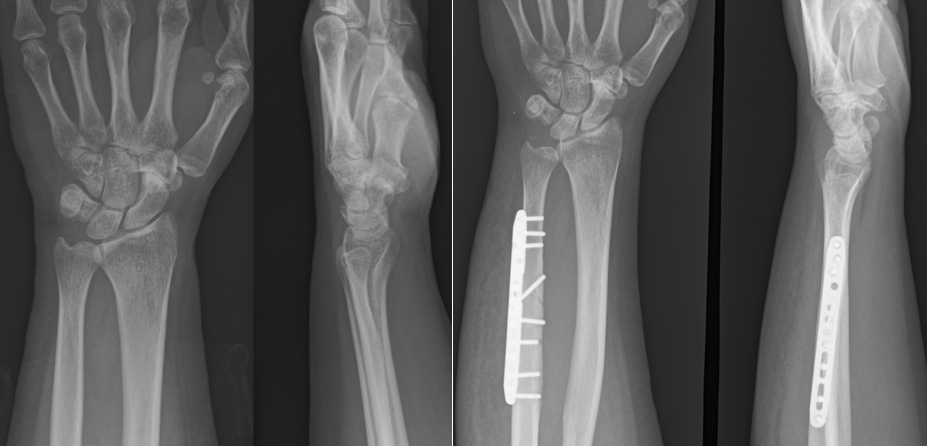

手術は関節鏡視下TFCC縫合術(TFCC関節包縫合術、経骨孔TFCC縫合術)、手関節鏡視下デブリドマン、TFCC再建術、尺骨短縮骨切り術、鏡視下尺骨遠位端部分切除(Wafer procedure)などがあります。各術式は年齢、性別、利き手側、スポーツや活動レベル、受傷機転、罹病期間、症状、身体所見などの他、画像評価によるTFCCの状態や突き上げ症候群の有無、DRUJの状態など総合的に評価して決定していきます。手術後は3~6週間、外固定を行います。また、リハビリテーションを行います。状態次第ですが、術後3~6か月程度で日常生活動作やスポーツ復帰が可能となります。

【尺骨短縮骨切り術(術前と術後)】